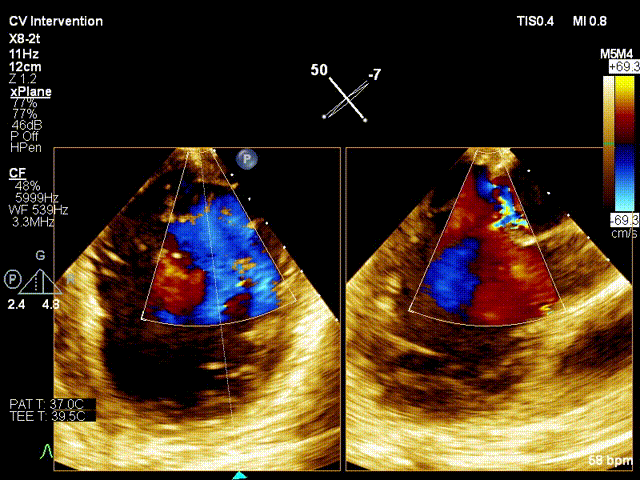

行TEE示:二尖瓣P2脱垂并累及部分P3区(DMR4+)、后叶腱索断裂、二尖瓣口舒张期几何面积 5.25cm2、收缩期二尖瓣口偏心性反流束缩流颈宽度8.0mm、PISA定量瓣口EROA=0.65cm2。STS评分13.009%。

术前X-plane